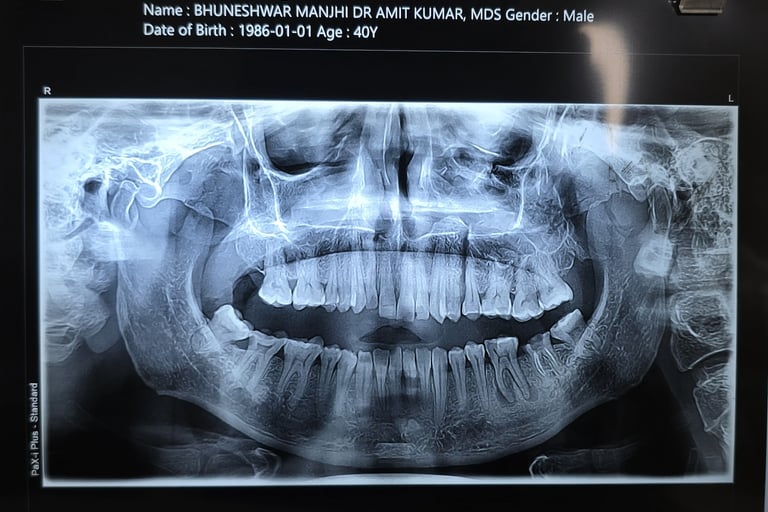

Diagnosis Done:

Clinical check-up

X-ray / OPG

CT Scan (if needed)